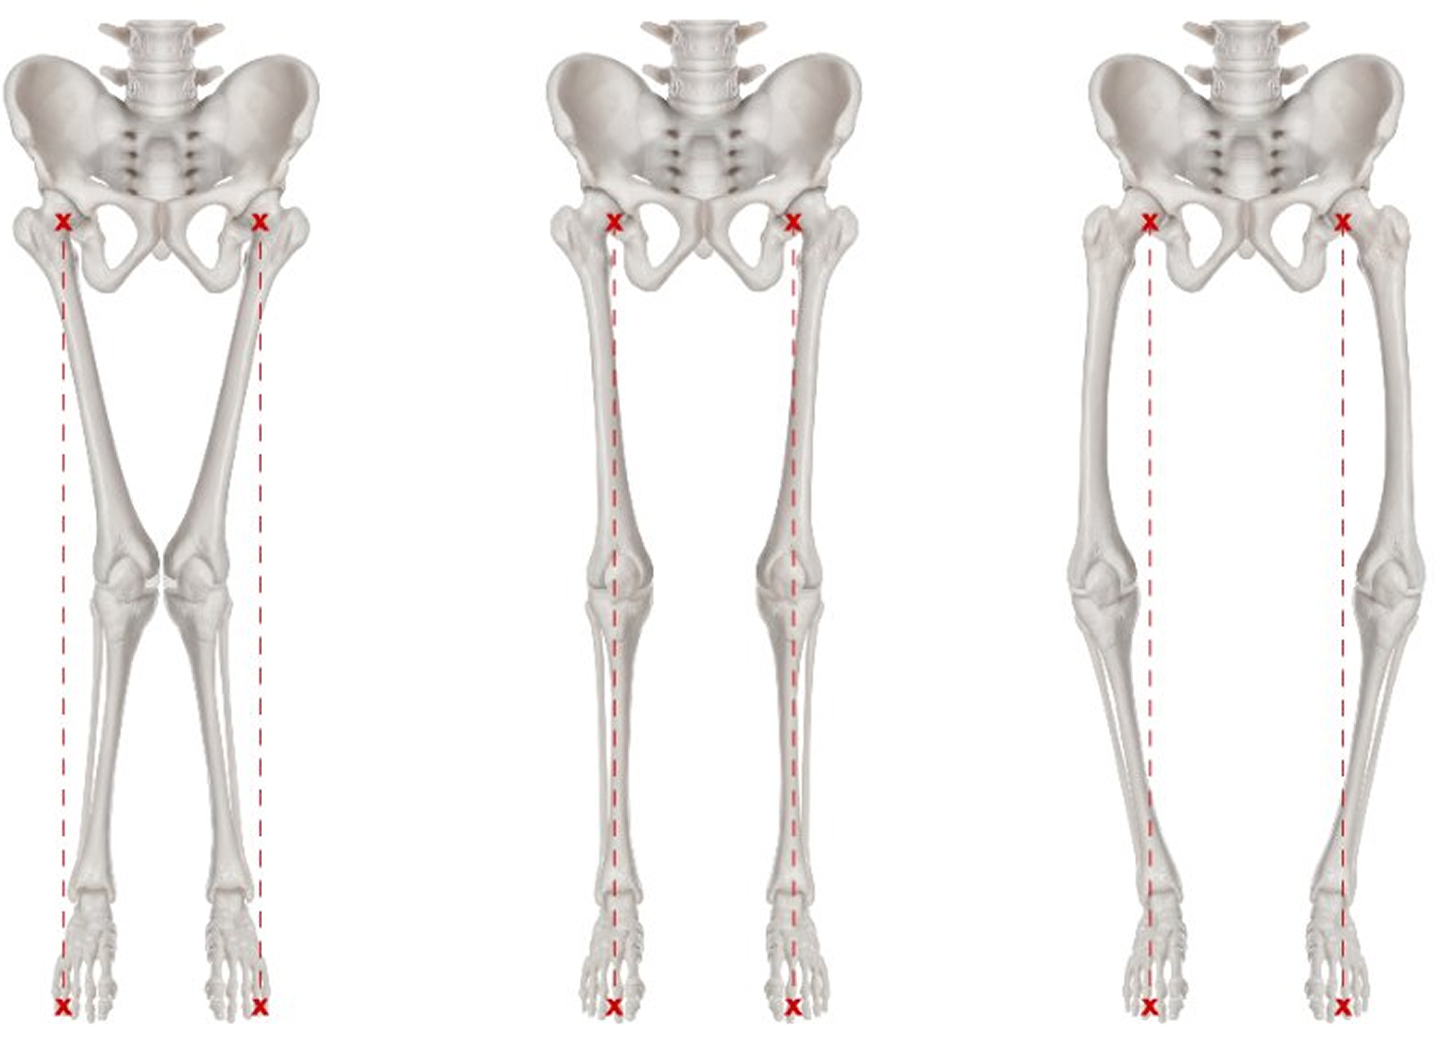

O脚・X脚とは?

O脚(ガニ股)、X脚(内股)ともに両膝が外側・内側に彎曲した状態の事を指します。